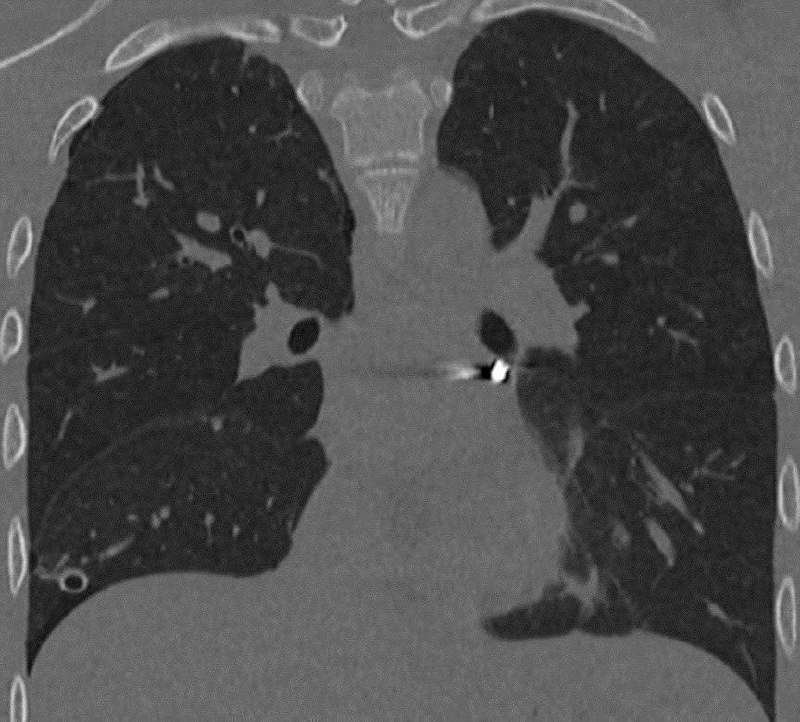

🫀В Подмосковье спасли подростка с пулевым ранением в сердце — друзья случайно выстрелили в него из пневматического ружья.

Медики обнаружили пулю в наружной оболочке сердца и провели экстренную операцию. В итоге, несмотря на сложность, пулю удалось извлечь без единого разреза.